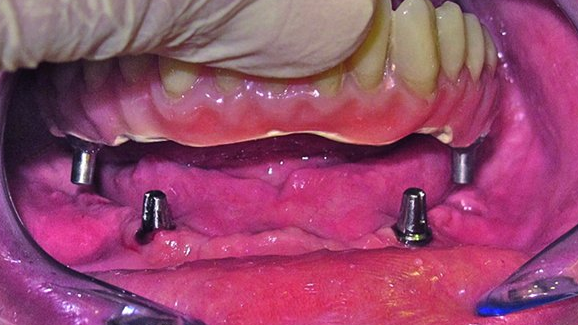

Un patient âgé de 52 ans, présentant un os mandibulaire fortement endommagé, a été traité en posant quatre implants courts. Deux implants SHORT (4,5 x 8 mm) ont été insérés en remplacement des canines, et deux implants ULTRA SHORT® (4 x 5 mm) ont été insérés dans les sites occupant la place des premières molaires (Fig. 1). Les implants ont été placés au cours d’une procédure chirurgicale en deux temps, puis ont été désenfouis après un temps de cicatrisation de trois mois (Figs. 2 et 3).

Un mélange fluide de résine pour prothèse dentaire a été coulé dans le moufle en silicone au travers de la découpe ou de l’ouverture réalisée à l’avant du masque lingual. La polymérisation définitive a été réalisée alors que le moufle en silicone et le modèle étaient maintenus sous une eau chaude et une pression d’air de 3 bars. Après la polymérisation, la prothèse Trinia a été retirée de son moufle en silicone, puis terminée et polie de manière conventionnelle. La phase clinique s’est poursuivie par la dépose des piliers temporaires du patient, puis deux piliers fraisés, tout au moins au début, ont été insérés partiellement dans la prothèse. Au besoin, ils ont été stabilisés par une application de vaseline, avant d’être portés en bouche avec la prothèse et insérés dans le puits de l’implant correspondant (Fig. 8). L’ajustage partiel des piliers dans la prothèse a facilité l’insertion initiale dans les puits implantaires (Fig. 9). La prothèse a ensuite été retirée afin de procéder à l’insertion définitive des piliers en titane, en tapant directement sur ceux-ci. Cette procédure d’insertion a été poursuivie avec les autres piliers jusqu’à ce que tous aient été insérés définitivement (Figs. 10 à 12).